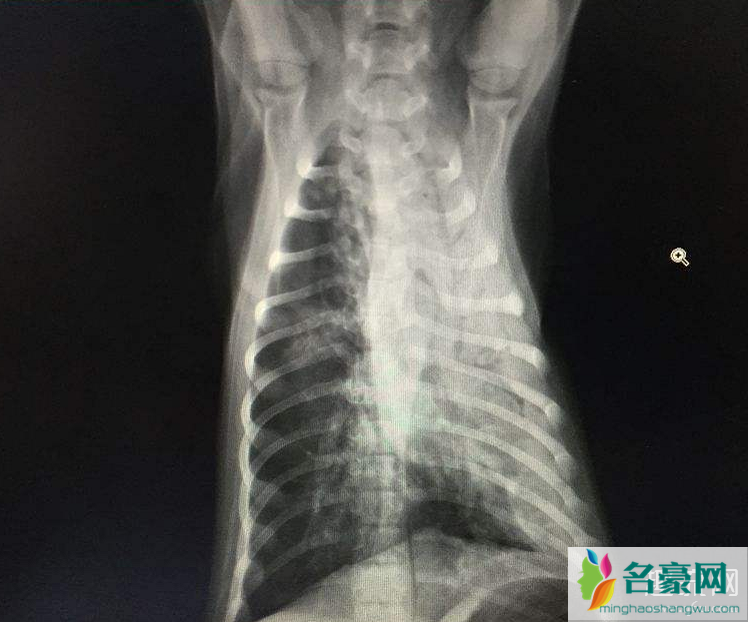

据央视新闻客户端,香港特区政府渔农自然护理署(渔护署)发言人28日凌晨发布消息称,一条居于新冠肺炎确诊者家中的狗对有关病毒测试呈弱阳性反应。渔护署于26日接获卫生署消息称,一名新冠肺炎确诊者的狗需交予渔护署处理。渔护署人员同日傍晚到大坑一住所接走这条狗,随即送往港珠澳大桥口岸动物居留所,并从其口腔,鼻腔及肛门抽取样本进行新型冠状病毒测试。结果反应其口腔及鼻腔的样本在测试中呈弱阳性反应。发言人提醒畜养宠物人士,须经常保持良好卫生习惯,当与宠物接触后,应使用肥皂和水或酒精洗手液彻底清洁双手;畜养者外出应佩戴口罩。